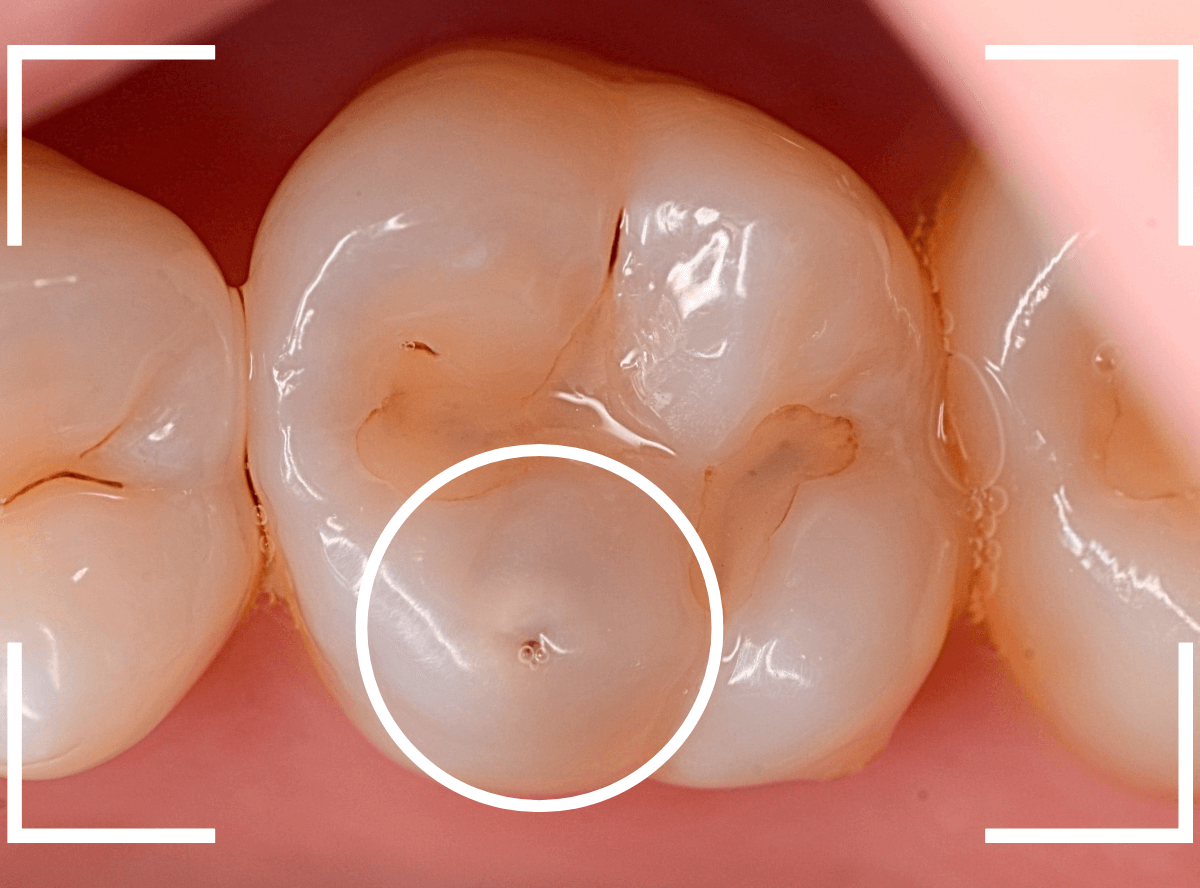

Case.11 治療をするべきか悩むケース

日々、診療をしていると、治療をすべきか、経過観察すべきか悩むケースによく当たります。

歯科医によって虫歯の数が違った!という話を聞きますが、こんなケースが多いのではないかと思います。

見た目は問題なさそうな所見です。

歯石除去時に黒い点が見つかりました。

見た目だけの小さな点であれば、経過観察でよいかと思うのですが、

- 歯と歯の間(隣接面)→虫歯が進行しやすい場所

- 黒い点がひっかかる→虫歯が進行している可能性

という点が気になります。

何はともあれ、レントゲン写真で確認します。

黒い点の前後がボヤっと黒っぽく写ります。

何かありそうにも何もなさそうにも見える、あいまいな写り方です。

あとは、患者さんに説明して削って中を調べていくしかありません。

患者さんの同意を得られましたので、慎重に削って中を見てみると、手前の歯からも虫歯が見えてきました。

手前の歯は中の方まで虫歯が進行しているのがわかります。

最終的には、元々つまっていたレジンやインレーを外して、しっかり中を調べて治療する事になりました。

すると、その後ろの大臼歯のレジン部にも虫歯が見つかりました。

虫歯がより深く進行する前に処置できてよかったかと思います。